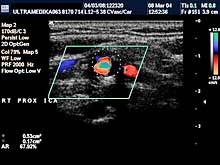

A) Krvni sudovi vrata

Vrsta i sadržaj pregleda:

- Pregled velikih krvnih sudova vrata CD i CPA

modom (obavezno karotidnih i vertebralnih arterija celim tokom).

Pregled podrazumeva procenu ukupne debljine krvnih sudova (indirektna

procena koronarne bolesti), procenu stepena suženja, karakteristika aterosklerotičnog plaka, procena hemodinamike i postavljanje

indikacija za operativno lečenje.

Primenjena tehnika:

- Sono CT,

- XRes,

- 2D Broad band,

- Broad band - CD,

- CPA ,

- CPD.

Preporučeni pregledi:

- nakon 45. godine starosti,

- obavezno ako postoje

faktori rizika

(hipertenzija, pušenje, stres, poremećaj nivoa masti u

krvi, kod sumnje da postoji koronarna bolest),

- kontrola na 6-12

meseci.